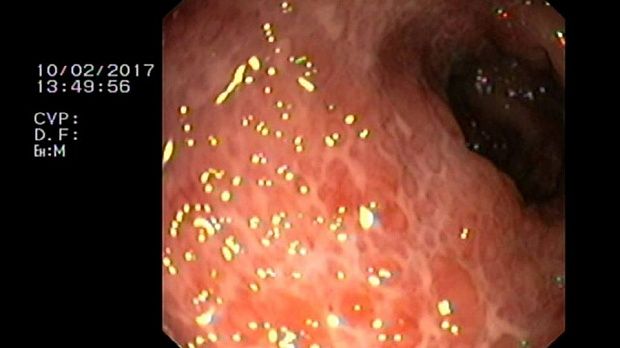

2 мл ( это мин сум, а мы делаем до 10 мл 3% перекись+200 мл физ раствора